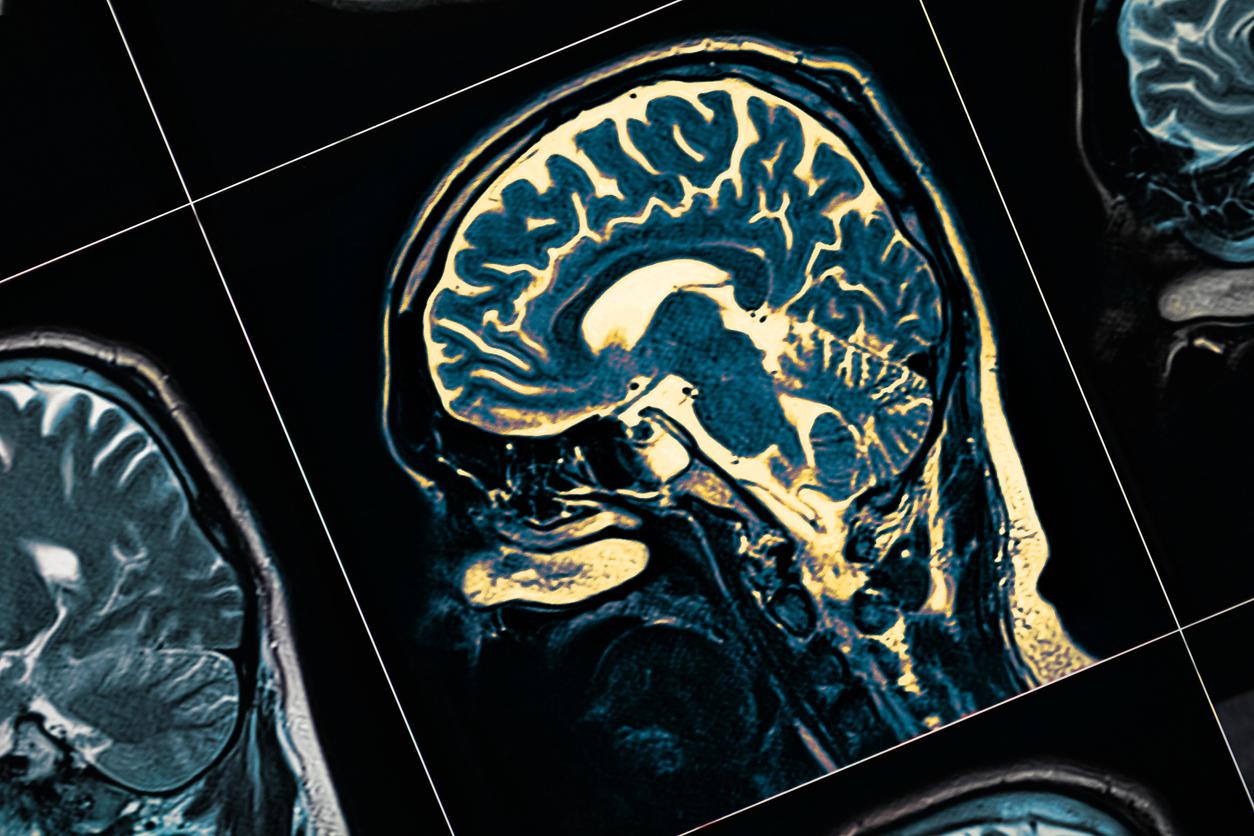

Il mesure moins de 5 millimètres et il fait pourtant des ravages : le microplastique. Il s’agit d’une particule de plastique ayant une taille inférieure à 5 millimètres. Dans la nature, il est extrêmement néfaste pour l’environnement, la faune et la flore mais aussi pour la santé humaine, dont notre cerveau.

Selon une équipe de chercheurs sud-coréens, les microplastiques réussissent à entrer dans le cerveau et s’accumulent dans les cellules microgliales, des petites cellules immunitaires du système nerveux central. Leur fonctionnement est ainsi perturbé, elles finissent par mourir et le cerveau n’est plus protégé. Les travaux des scientifiques viennent d’être publiés dans la revue Science of The Total Environment.

Pour parvenir à leurs résultats, les chercheurs ont mené leur travaux sur des souris. Ils ont constaté que les microplastiques inférieurs à 2 micromètres - soit 0,002 millimètres - de diamètre pouvaient traverser la barrière hématoencéphalique. Cette dernière est une barrière physiologique qui protège notre cerveau des toxines et de beaucoup d’autres agents pathogènes présents dans le sang. Quand on ingère des microplastiques donc, ils entrent dans notre cerveau par cette barrière hématoencéphalique et s’accumulent ensuite dans les cellules microgliales. Celles-ci sont perturbées, meurent et ne protègent plus le cerveau.